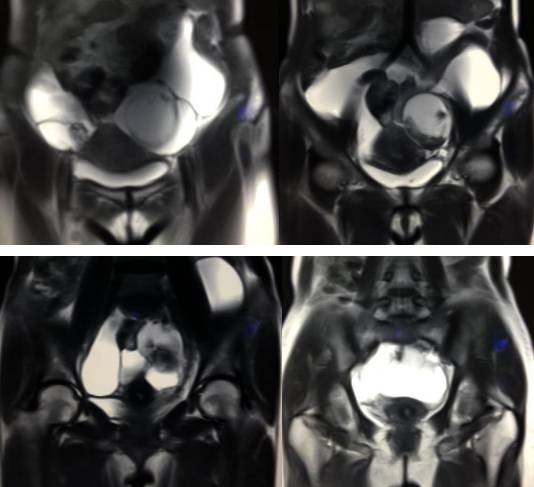

MR检查:

病理结果:黄体血肿

黄体血肿为正常排卵过程中,卵泡层破裂,引起出血,较多的血液潴留在卵泡或黄体腔内形成血肿。

正常黄体直径为15mm左右,以后转变为白体,并在下一个周期的卵泡期自然消退。若黄体内出血量较多,则形成黄体血肿,或称黄体内出血,出血性黄体。黄体血肿多为单侧,一般直径为40mm,偶可达100mm,黄体血肿被吸收后可导致黄体囊肿,较大的血肿破裂时可出现腹腔内出血,剧烈腹痛、少量阴道流血和腹膜刺激征,不易与宫外孕区别。

根据时间不同MR信号也有所不同,TIWI脂肪抑制序列可以鉴别脂肪和出血。

卵巢囊肿:呈均匀的T1WI 低信号,T2WI 高信号,边界清楚,壁薄,大多数病灶直径≤5 cm,但囊肿的起源及定性诊断困难。

巧克力囊肿:常呈多发的单囊或多囊改变,病灶大小不等,囊壁厚薄不均,囊内信号复杂,囊内或各囊腔间血液因出血时期不同,信号常呈多样性,囊肿内反复出血、破裂,形成相互粘连的多房性囊肿,是其较为特征性的表现。

在鉴别卵巢畸胎瘤、出血性囊肿或巧克力囊肿时,MR 脂肪抑制T1WI 可明确肿块内高信号成分是脂肪还是出血,同时由于脂肪组织与非脂肪组织的共振频率不同,在两者交界处沿磁场频率编码方向出现化学位移伪影,但出血性囊肿与巧克力囊肿的鉴别有时较为困难。